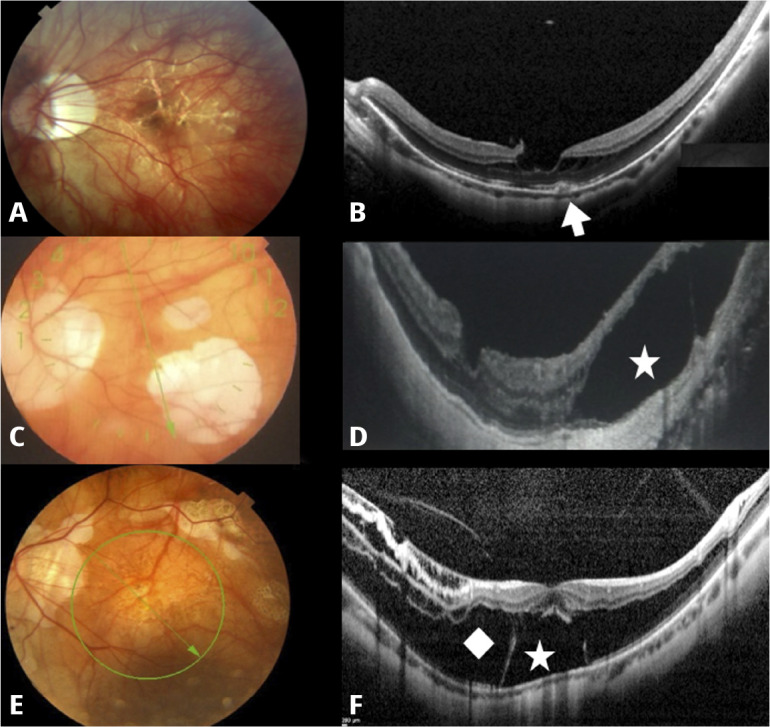

Management of myopic traction maculopathy.